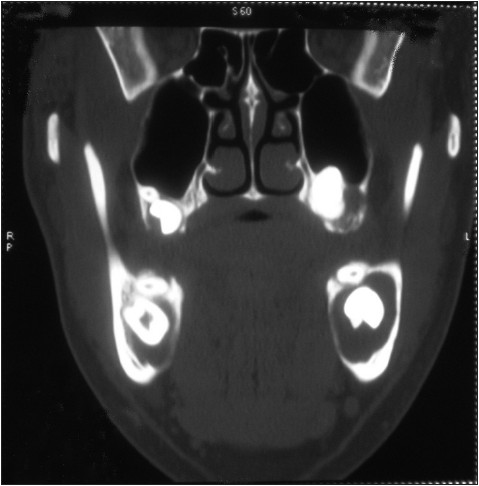

| Figure 6: The coronal view of mandible in CT image shows bilateral lingual bone perforation

Click here to view |